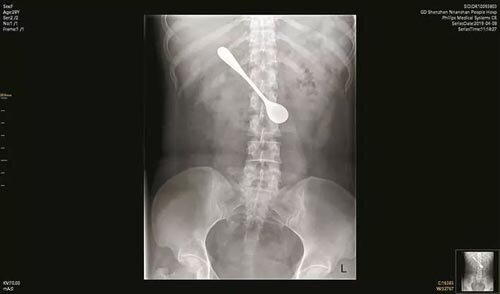

Посиживая у себя в квартире, Лили наслаждалась вкуснейшей рыбкой. Жадно поглощая любимые морепродукты женщина вдруг почувствовала, как что-то мешает ей в горле. Методом дедукции было выяснено, что посторонний объект, находящийся в горле - это рыбья кость. Я думаю у всех были такие моменты, ощущение слегка неприятное. Оставался вопрос, как более эффективно инородное тело извлечь? Ответ на него просто великолепный...

Месье и Мадмуазели, прошу любить и жаловать - госпожа Чайная Ложка!

Жительница поднебесной решила именно ей "выловить" кость. При яростных ковыряках в горле ее подвели жирные от рыбки пальчики и ложка благополучно заняла почетное место рядом с засевшей внутри косточкой. Казалось бы, пора уже обратиться за помощью к китайским друидам, только вот зачем?

- "Дискомфорта вроде не ощущаю, ложка как родная засела, да и праздники скоро! И тааак сойдееет!" Именно так Лилька и подумала, по этому Цинмин, да и еще пару дней, она провела с ложкой внутри. Та, в свою очередь, благополучно добралась до кишечника.

До больницы она все таки добралась, где 13-сантиметровый агрегат из нее и извлекли. Врачи конечно были знатно шокированы таким поведением, ведь ложечка позвала на вечеринку друзей, в виде эрозии и отека кишки. Но бабенку вылечили и чувствует она себя после заглатывания продолговатых предметов просто превосходно.